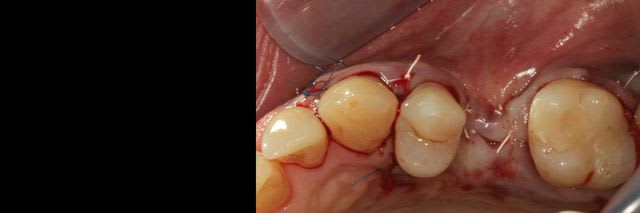

J'ai décidé de réaliser un lambeau déplacé latéralement associé à un conjonctif enfoui le jour de l'extraction afin d'avoir des tissus mous de meilleure qualité pour la greffe, ci joint les photos à 6 semaines.

Bon ben voilà j'ai réalisé une ROG avec une membrane PTFE armé titane.

bien sûr les photos sont dans le désordre encore une fois ;)